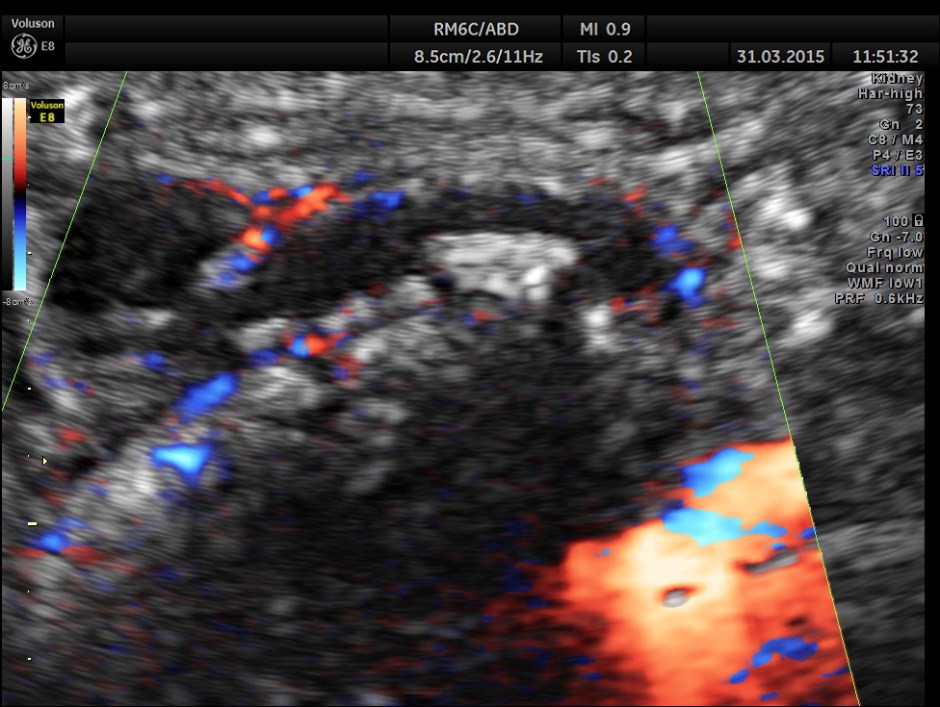

Colour Doppler shows vascularity of the wall . It was non pulsatile and non collapsible.

Now this looks more like an inflamed appendix with a prominent fecolith of size 11.4 mms , throwing a shadow.

The following pictures are with a high resolution probe.

Careful attempt to establish any continuity of the dilated ” tube ” to the ureter or dilated pelvis , showed that the dilated structure was separate from the right ureter .